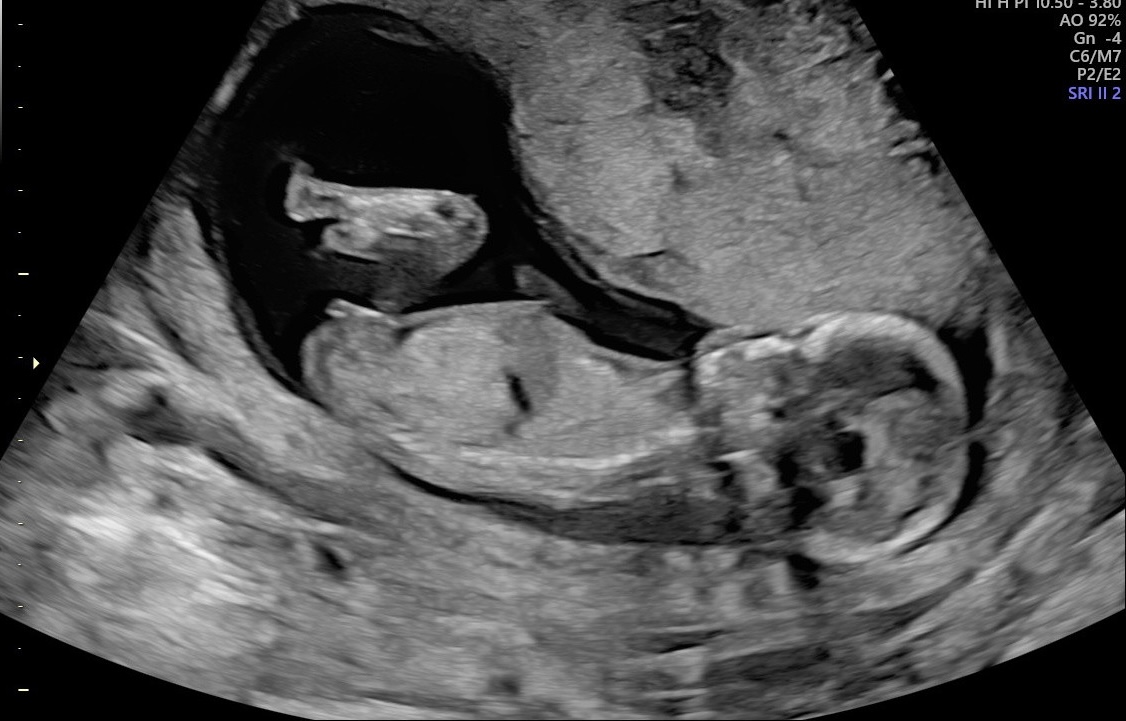

Hi! Potty shot taken at 14 + 0 days. Think it was more like 13 weeks & 5 days. What do you think, girl or boy?

My gut (on both!) pictures is girl, did the tech have an opinion??

I'd definitely lean girl - especially with the nub being that direction on the second pic! ;)

I'd say girl. The nub especially looks very girly.

Ahhh the tech said also girl… but it’s early right? 14 weeks (13+6d)

I can’t believe it is true…:XX:! do you think there is still time to change?

Ahhh, see the techs see far more than we see and if they're saying girl, then I'd be very happy to hear that. :cheer: :cheer: :cheer: It' s not a guarantee but it's very very very encouraging to hear that.

The end of the 13th week is NOT too early. not at all. 10/11/ and the start of the 12th week are too early. End of the 13th week is getting pretty sure!

I have, over the years, seen 3 times where a baby I was sure was a girl at the end of the 13th week, the nub rose and it was a boy. But in those cases the tech did not have an opinion - the tech's opinion is the most important becuase they have a long time to look and can see from every angle.

We can't say 100% at this point, but if the tech thought girl, Anna, I would be very very very happy (and I am very very very happy for you!)